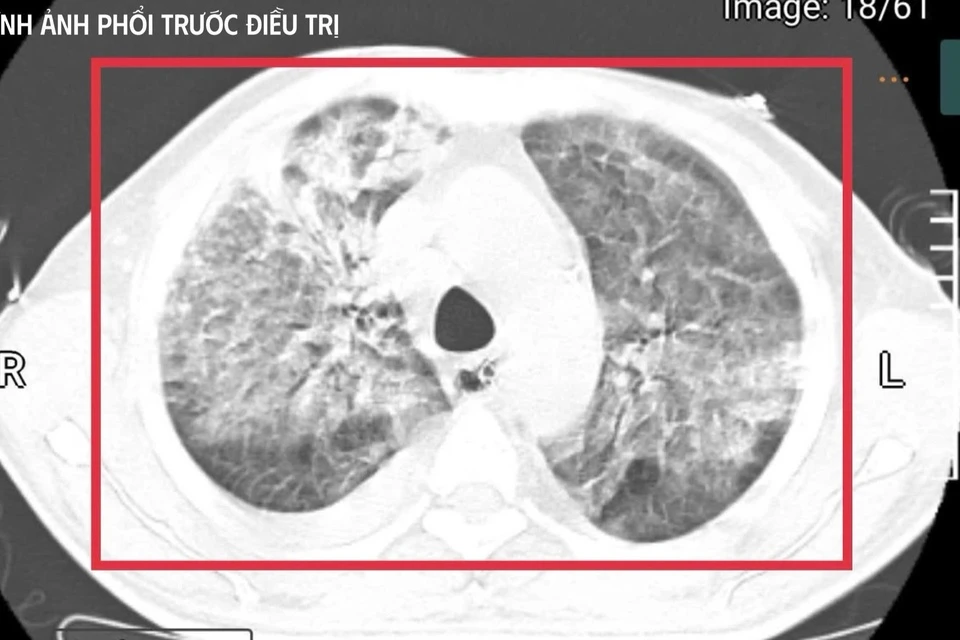

Bệnh nhân 35 tuổi từ vùng lưu hành vi khuẩn mang bệnh Whitmore trở về trong tình trạng nguy kịch, sốc nhiễm khuẩn, suy đa tạng, thân nhiệt hơn 41°C và hôn mê sâu.

Tại đây, bệnh nhân được đặt nội khí quản thở máy; kết quả cấy máu xác định nhiễm Burkholderia pseudomallei - tác nhân gây bệnh Whitmore. Dù được điều trị ban đầu, tình trạng vẫn diễn tiến nặng nên gia đình xin chuyển về Việt Nam để tiếp tục điều trị. Nhưng chỉ sau ít ngày, người đàn ông này rơi vào sốc nhiễm khuẩn, suy đa tạng, sốt cao liên tục, rối loạn ý thức và được chuyển gấp ra khoa Cấp cứu, Bệnh viện Bệnh Nhiệt đới Trung ương (Hà Nội).

Theo bác sĩ Kim Anh, đây là một trong những thể tối cấp của Whitmore, nhiễm khuẩn huyết nặng, suy đa tạng, rối loạn chuyển hoá sâu và nguy cơ không qua khỏi rất lớn trong thời gian rất ngắn nếu không được hồi sức tích cực ngay lập tức.

Đội ngũ bác sĩ đã phải "chạy song song" nhiều can thiệp: an thần sâu để kiểm soát kích thích và bảo vệ não, hạ thân nhiệt chủ động nhằm khống chế tình trạng tăng thân nhiệt ác tính, thiết lập đường truyền trung tâm, theo dõi huyết động liên tục, điều chỉnh toan - điện giải, phối hợp kháng sinh theo phác đồ điều trị Melioidosis và tiến hành lọc máu liên tục nhiều ngày để hỗ trợ chức năng thận, loại bỏ độc chất và giảm gánh nặng viêm.

Sau khoảng 3 ngày hồi sức cao độ, bệnh nhân bắt đầu cắt sốt, các chỉ số viêm giảm dần, huyết áp ổn định hơn với nhu cầu vận mạch giảm, chức năng gan thận cải thiện, tri giác dần hồi phục. Người bệnh cai được thở máy qua mở khí quản, tập lại hô hấp tự nhiên và phục hồi vận động.

Trong 3 tuần điều trị tích cực tại khoa Cấp cứu, các bác sĩ tiếp tục tối ưu kháng sinh, kiểm soát chặt chẽ đường huyết, hỗ trợ dinh dưỡng và phục hồi chức năng sớm. Người bệnh hồi phục từng bước, tỉnh táo hoàn toàn, tự thở khí phòng với SpO₂ 99%, huyết áp 130/80 mmHg, cơ lực chi trên đạt 5/5, chi dưới 4/5, đủ điều kiện ra viện và tiếp tục theo dõi ngoại trú.